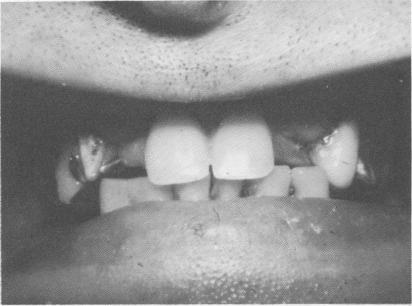

A 52-year-old man with an extremely powerful bite had broken a few of the anterior maxillary teeth off his removable partial denture (Fig. 10-188). His remaining teeth showed rampant caries (Fig. 10-189).

Fig. 10-188. A broken removable partial denture with two lateral incisor teeth missing from it is all that the patient had been wearing.